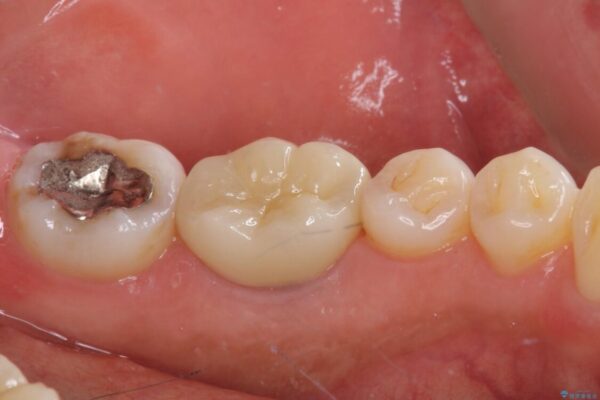

以前他院にて処置をした歯の歯肉からの出血するとのことで来院された患者様です。

以前むし歯治療をした後から定期的に痛むことがあるとのことで、レントゲン写真より神経組織が失活していることが予想されました。

銀歯を外すと神経組織の一部が取り除かれており、歯根に付け根に穴が空けられている状態でした。

治療前

• むし歯で歯茎から血が出てくる オールセラミッククラウンでの補綴治療 治療前画像